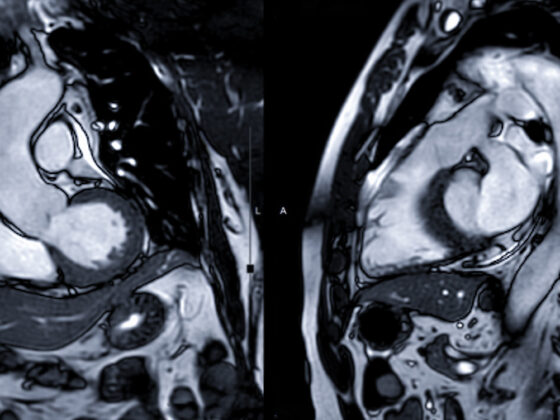

• Verdacht auf koronare Herzkrankheit

Stress-Echokardiografie, MR Herz oder Computertomografie Herz?

• Kardiologie

• Nuklearmedizin

• Radiologie